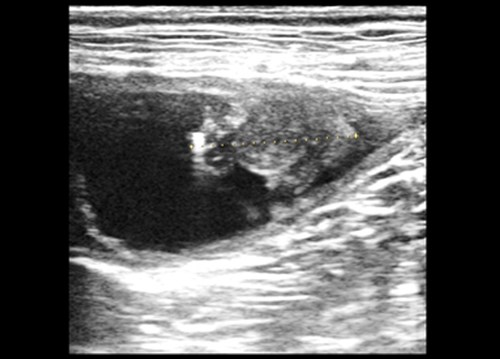

超音波検査

症例:膀胱腫瘍